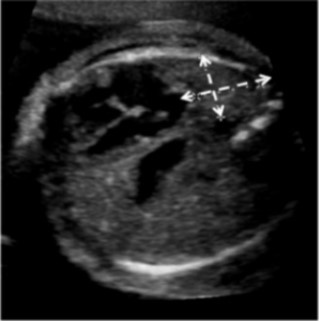

For each patient, the original ultrasound wherein the LHR had been calculated was reviewed, and the U/S LHR noted. A single reviewer (EP) analyzed these ultrasound images to determine the accuracy of of U/S LHR calculation. All practitioners in the Maternal Fetal Medicine department use the same technique for calculating LHR, the longest diameter method15. The images were reviewed to ensure that the cross-sectional area of the contralateral lung was measured at the four chamber view of the heart (Figure 1), the cross-sectional area was calculated with the longest diameter in the correct plane, the width was perpendicular in the correct plane, and the actual calculation was mathematically accurate. The U/S LHR values were then calculated by entering these measurements into the LHR calculator on perinatology.com. The inaccurate calculations were categorized based on the reason for inaccuracy: not measured at the level of the four chamber view of the heart, inaccurate calculation, poor images, no calipers, or oblique angle.

Figure 1.Fetal ultrasound demonstrating apropriate measurement of lung at the four-chamber view of the heart